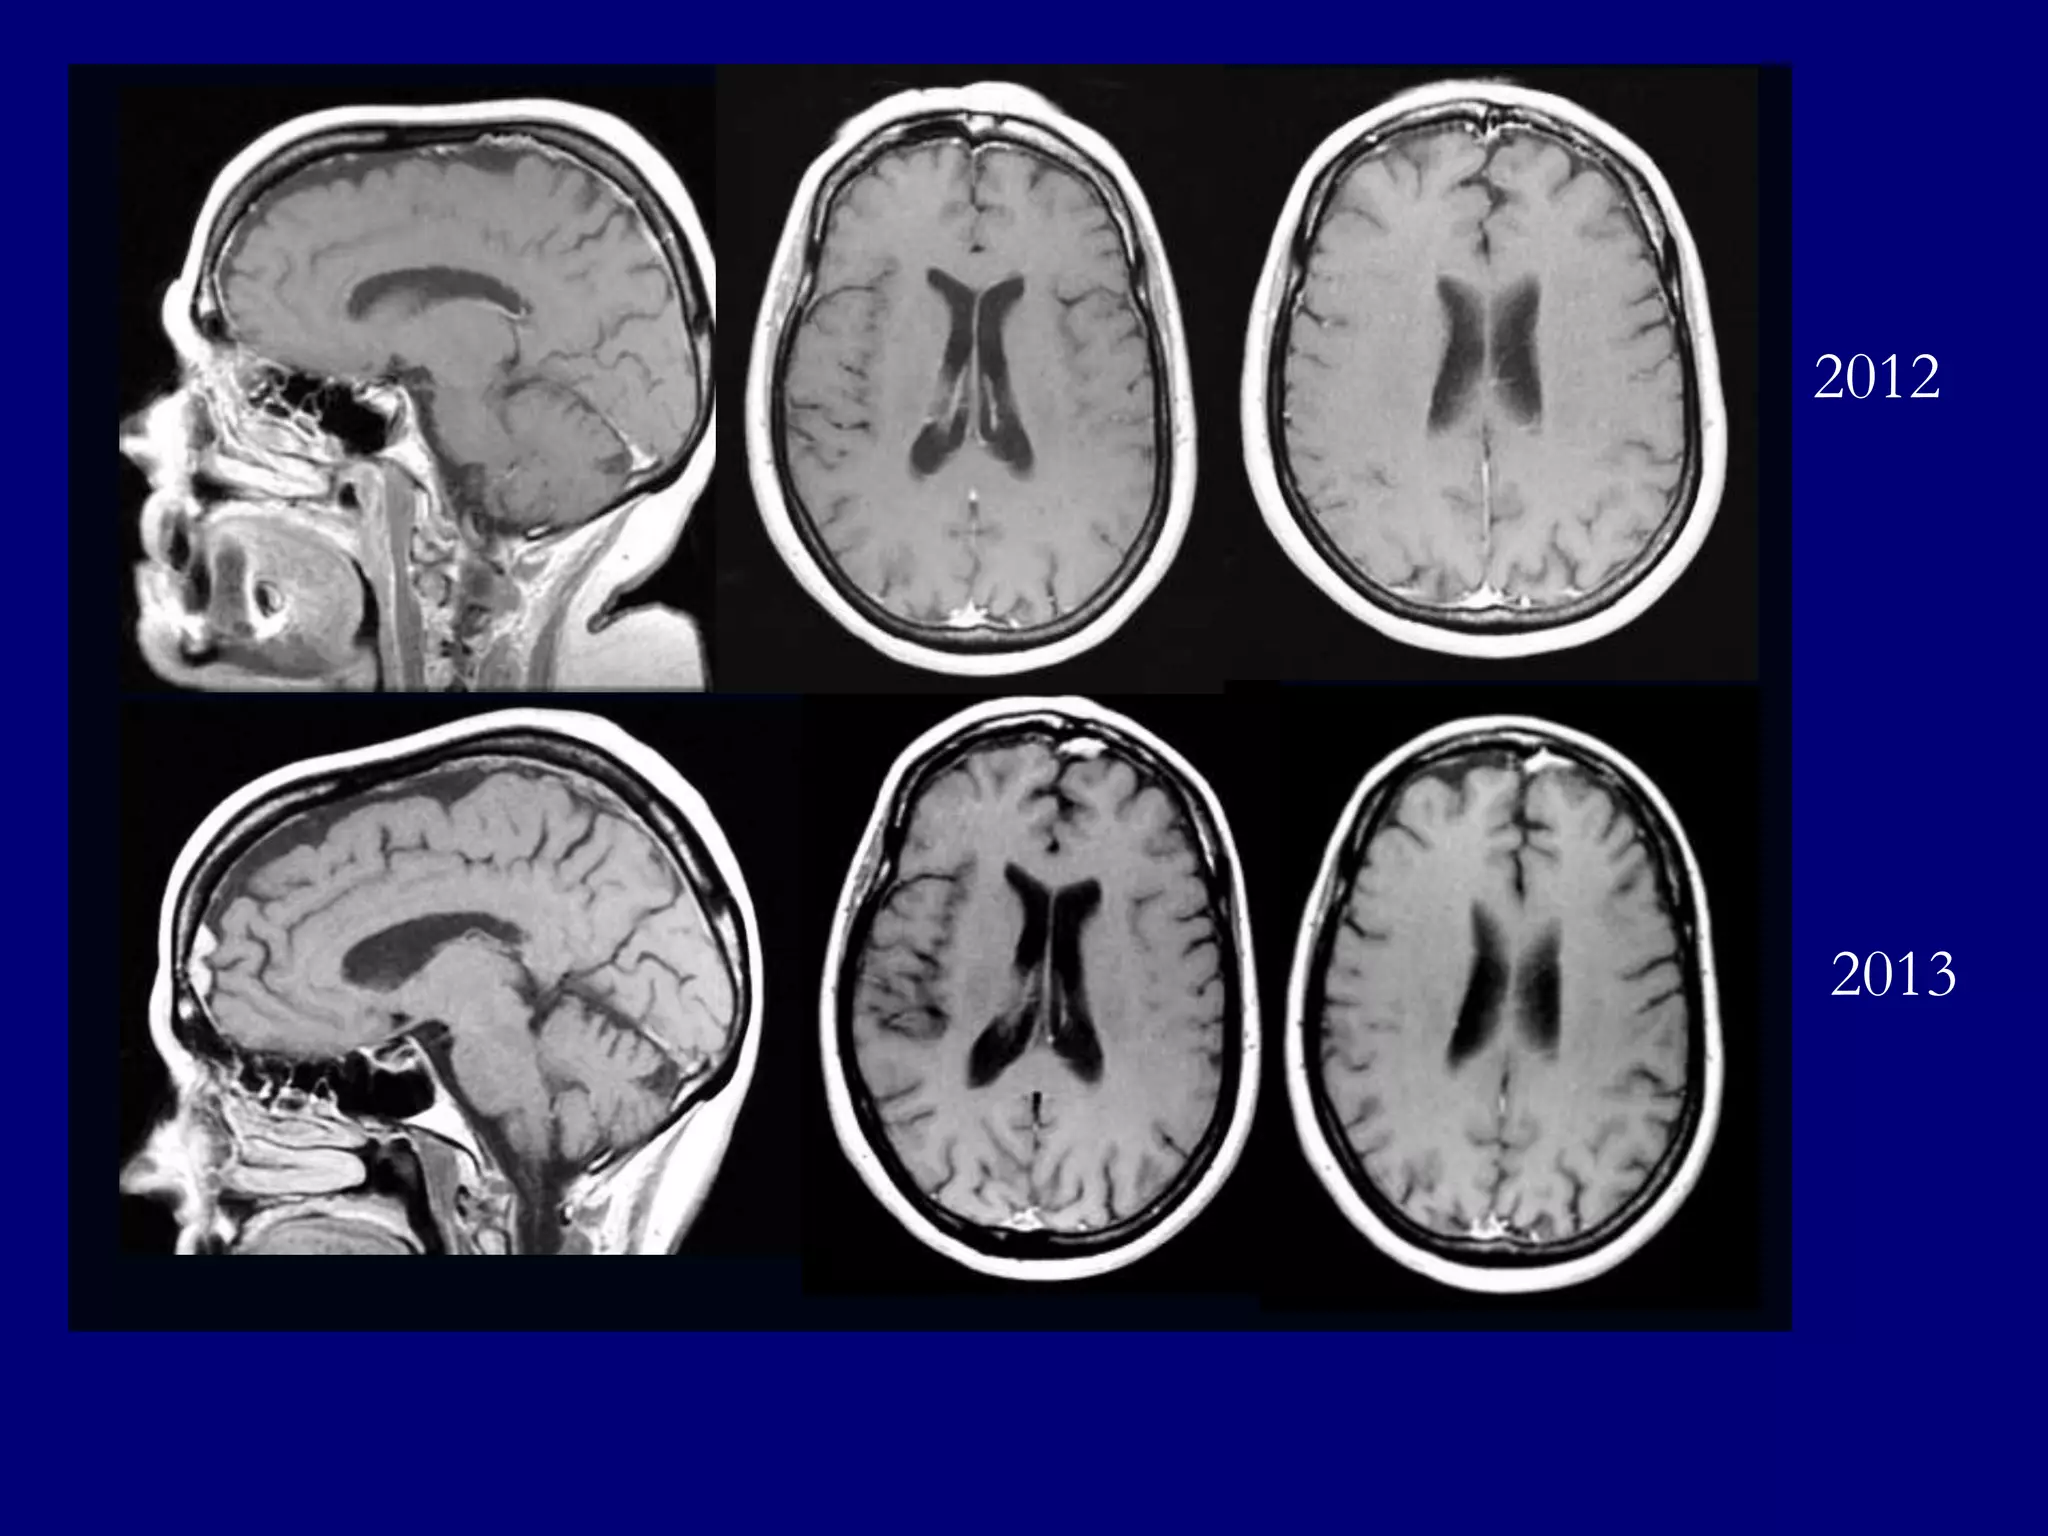

65-year-old female, with a past medical history

significant for obesity, hypertension, and multiple

sclerosis

A routine follow-up MRI for multiple sclerosis at

an outside facility revealed a new dumbbellshaped mass in the frontal area on the left

Patient referred for biopsy with differential

diagnosis of plasmacytoma, lymphoma, or dural

based metastasis

2012

2013

MRI 2012

T1-weighted post-gadolinium

MRI 2013

T2-weighted

FLAIR